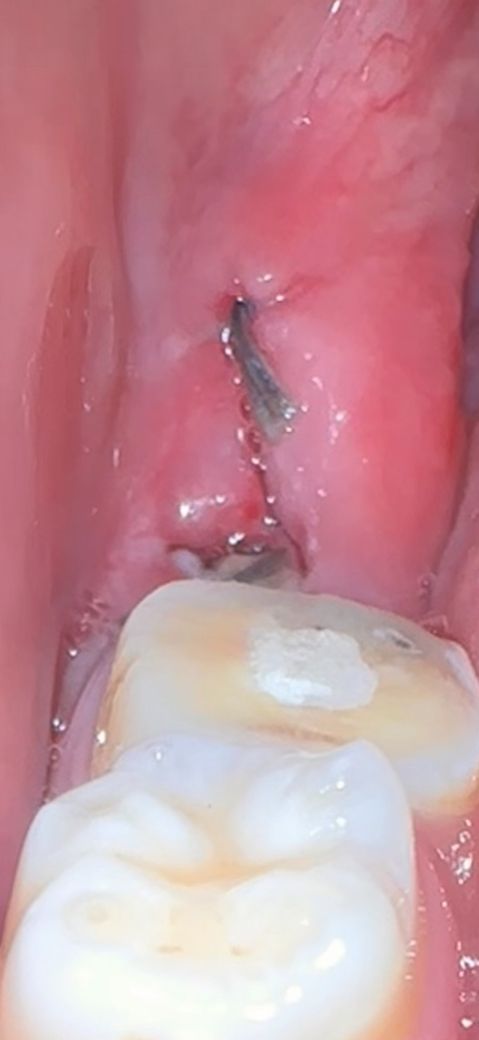

사랑니 발치 후 염증인지 아닌지 알려주세요..

사랑니 발치 후 7일 정도인데 괜찮은건가요

욱씬 욱씬 한 것 같기도 하고 사랑니 앞 부분이 신경치료 하고 있는 부위여서 그렇게 느껴지는건지 잘 모르겠어요..

사진상으로 보면 사랑니 발치를 한곳이 잘 아물고 잇는거 같으니 자극만 가지 않도록 해주시면될것같습니다.

염증 반응으로 보이지는 않습니다. 실밥 빼고 나시면 괜찮아보일 것 입니다. 관리잘해주시면 됩니다.

사진으로 봤을 경우에는 발치한 부위가 잘 아물고 있는 것으로 보입니다. 발치한 부위는 자극이 되지 않는 것이 치유가 되는데 도움이 됩니다.

사진상 발치 후 일주일째의 치유상태 평균 정도로 보입니다 크게 걱정안하셔도 될 것 같습니다